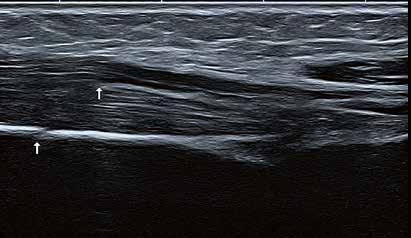

Hochauflösender Ultraschall in der Sportpraxis

Wie kamen Sie zur Sonographie?